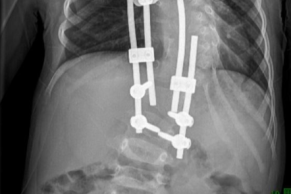

黄婆婆在 ICU 治疗

重症医学科马磊主治医师介绍说:黄婆婆由于年龄大,基础疾病多,存在多器官功能障碍,病情危重,入科后给予持续心电、血压、呼吸、氧饱和度监测,无创呼吸机辅助通气,行深静脉穿刺置管术监测 CVP,予无创心功能监测。

予血管活性药物提升血压、改善器官灌注压,予持续血液净化治疗(CRRT),予以调脂、抗凝、降糖、维持电解质和内环境稳定等对症支持治疗。